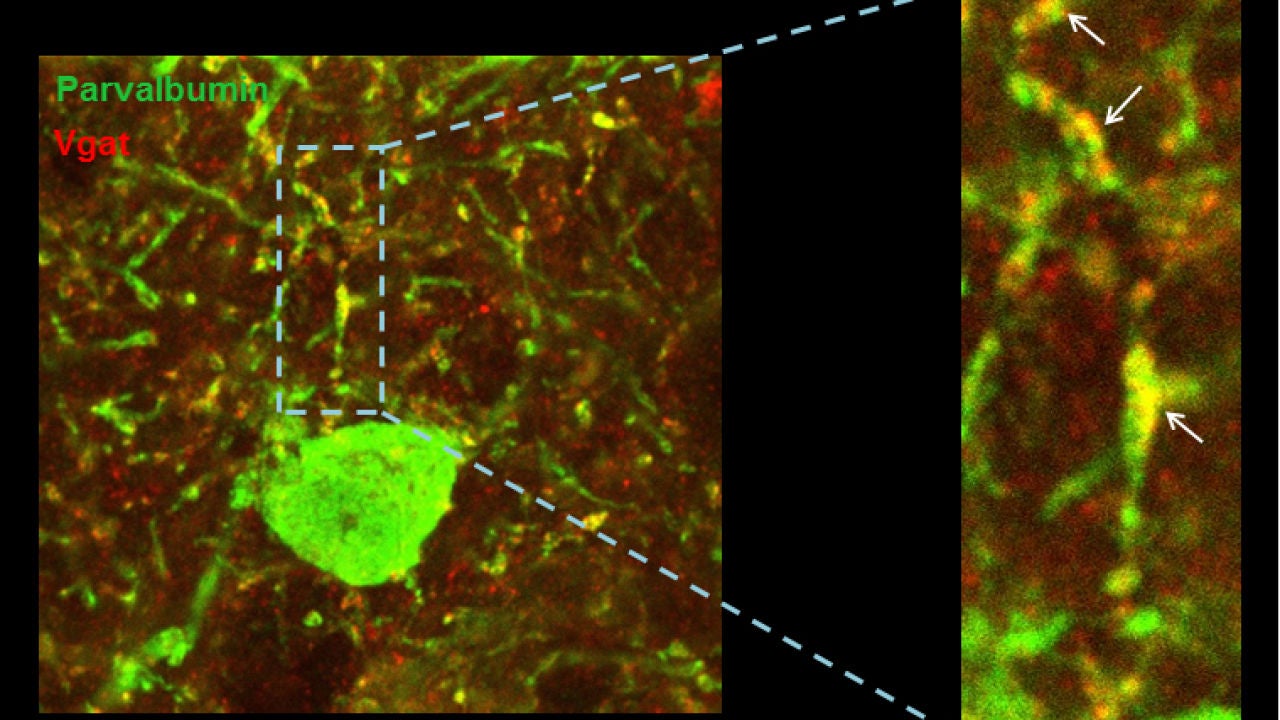

Las científicas se han centrado en uno de los genes relacionados con el síndrome de Down. Mediante experimentos con modelos animales que sobreexpresan el gen candidato, demostraron que el exceso de este gen provoca cambios muy sutiles en el equilibrio excitación/inhibición y estos llevan a una reducción notable de la actividad y sincronización de las neuronas excitadoras en la corteza prefrontal.

Es decir, que cuando este gen se encuentra sobreexpresado, reduce el nivel de descarga de las neuronas y altera el ritmo en las ondas de alta frecuencia de la corteza cerebral. Es más, observaron que el problema radica en unas neuronas que se encargan de controlar la inhibición. En resumen, si hay menos actividad y existe una desequilibrio en las frecuencias de las ondas cerebrales en síndrome de Down es debido a cambios en la conectividad de las neuronas que deben controlarlas.

El estudio ha combinado experimentos de electrofisiología e histología con un modelo computacional que emula el circuito neuronal de la corteza cerebral de forma virtual. “Hemos identificado alteraciones anatómicas y funcionales, y a través de un modelo computacional hemos demostrado cómo dichos déficits pueden explicar las observaciones experimentales” comenta Sánchez Vives, jefe del equipo de Neurociencia de Sistemas y coinvestigadora principal del estudio.